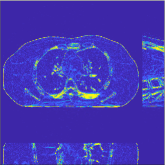

III-B3 Generalization Capability Comparisons between a “Denoising” Deep NN and the Proposed PWLS-ST- Method

This section compares the generalization capabilities between the proposed MBIR method, PWLS-ST-, and a denoising deep NN, FBPConvNet [14], that are trained from the phantom data; in particular, we tested the trained PWLS-ST- and FBPConvNet models to phantom and clinical scan data. The results in Fig. 6 show that the non-MBIR FBPConvNet method has higher overfitting risks, compared to the proposed PWLS-ST- MBIR method. When tested on clinical scan data, PWLS-ST- achieves much more accurate reconstruction, compared to FBPConvNet. See Fig. 6(b). When tested on phantom data, FBPConvNet generates more unnatural features as the number of views reduces, although it gives lower RMSE values compared to PWLS-ST-. See zoom-ins in Fig. 6(a). The FBPConvNet results above correspond to those in the recent work [16] that FBPConvNet [14] generated some unexpected structures.